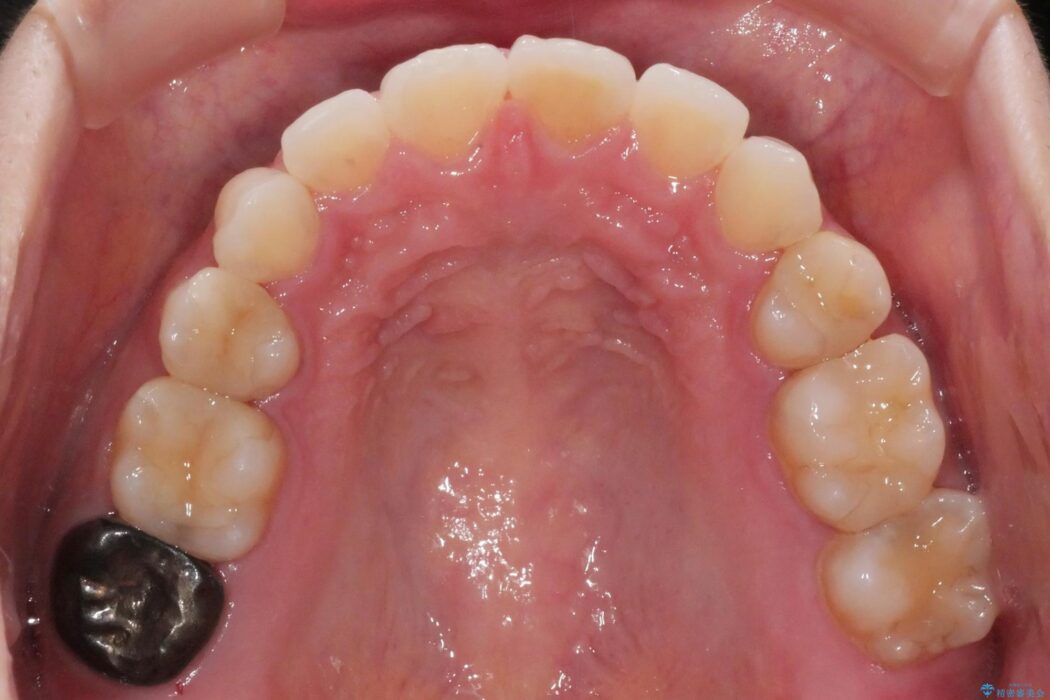

抜歯矯正後の後戻りについてご相談にいらした患者様です、

後戻りの程度としては軽度なので、治療期間としては短く終えることが出来ました。

前歯の正中線も改善され大変満足していただきました。